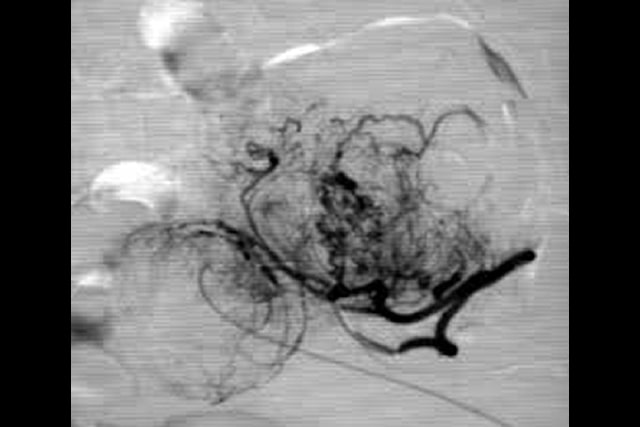

A embolização das artérias uterinas é uma técnica segura, introduzida por Ravina em 1995, posteriormente endossada por agências mundiais (NICE, FDA ..), é um método seguro. É doloroso na primeira semana após a embolização e tem um risco de amenorréia permanente (sem menstruação) de 3% nas pessoas com menos de 40 anos e 15% nas pessoas com mais de 40 anos.

A Radiofrequência Vaginal é um procedimento ambulatorial. É realizado com controle ultrassonográfico e o paciente fica sedado. Primeiro, é feita uma biópsia do mioma, que é analisada na anatomia patológica. O mioma é puncionado com uma agulha de radiofrequência e todo o mioma é tratado. Posteriormente pode-se verificar na mesma sala cirúrgica como a vascularização da mesma desapareceu. É um procedimento seguro, os controles serão feitos aos dois e aos 6 meses.